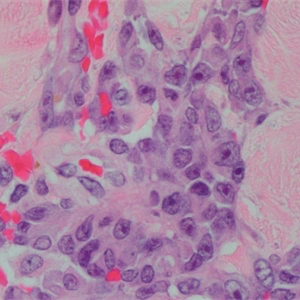

2. 多结节性出血性肿物,细胞形态从梭形至上皮样不等;

3. 上皮样区由大圆形细胞构成,细胞核分级相对高,细胞排列成片、小巢、条索或原始血管结构。

4. 肿瘤性血管形态不规则,通过血窦结构互相连通,并破坏浸润周围组织,有些区域血管的肿瘤性内皮细胞过多,形成出芽、突起或乳头;

5. 肿瘤细胞异型性明显,恶性程度高,核分裂象易见,瘤组织具有显著侵袭性;